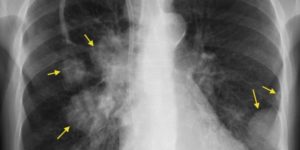

Видно ли рак легких на флюорографии или нет? Данный метод исследования не позволяет точно определить злокачественную опухоль, а позволяет лишь увидеть само новообразование. Врач делает снимки в прямой проекции. При необходимости делают боковые снимки, что позволяет определить какой именно рак:

- периферический рак лёгкого

- центральный рак легкого на рентгенограмме.

Так показывает ли флюорография рак? Да, рентгеноскопия позволяет увидеть врачу рентгенологу затемнение или просветление, контуры, полости новообразования. Да и сам пациент может просмотреть рентген и увидеть, так как чаще всего четко просматриваются заболевания органов дыхания.

При центральной форме ракового образования, на рентгенографии будет отображаться, что в легких присутствует расширенная сеть сосудов, а также имеются замутненные участки. Когда у легочной онкологии периферический характер, картина на рентгеновском изображении будет отображать присутствие четкой тени с неровными краями, от которой к корню легких отходят отростки в виде лент.

Как выглядит рак легких на флюорографии? Конечно, опухоль на снимке сложно распознать неспециалисту. Квалифицированный доктор может ее заподозрить по следующим признакам:

- Наличие уплотнения. Чаще всего оно одностороннее, отбрасывает тень. К нему могут примыкать тяжи. При этом заметно, что корни легкого будут несколько расширенными.

- Тень, которую отбрасывает уплотнение, разной формы. Но чаще всего именно шаровидной. Как правило, она имеет нечеткие края, вокруг нее может быть некоторая «лучистость».

Косвенные признаки

Не всегда на снимке видно новообразование в то время, как рак уже начинает развиваться. Квалифицированный доктор способен заподозрить это заболевание по ряду косвенных признаков:

- Гиповентиляция (недостаточная вентиляция) легких.

- Ателектаз легочных участков.

- Компенсаторное повышение воздушности примыкающих к нему отделов.

- Дистальное сближение сосудов (оно может происходить за счет сдавливания опухолью).

- Утолщение стенок бронхов.